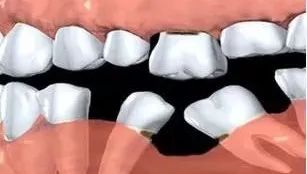

3、缺牙之後冇即時修復,引致兩側牙齒之間嘅空隙。

3.牙齒缺失之後應該盡早進行修補治療,兩側嘅牙齒向缺口傾斜後將會增加治療難度,需要先進行正齒治療將傾斜的牙齒直立消滅間隙後再進行修復治療。